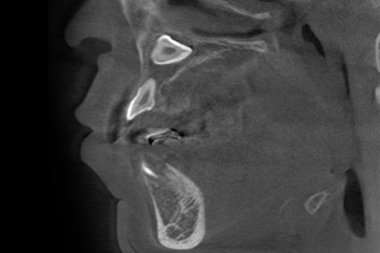

CT検査

3次元情報から、歯の位置・埋伏歯(歯冠の全てまたは一部が顎の骨や歯肉の中に埋まって出ていない歯)・過剰歯(決まった本数よりも多く歯が生えてくること)などを確認します。埋伏歯や過剰歯があると、歯が移動する際に適切な動きができなくなってしまうため、事前に不要な歯を確認しておく必要があります。また歯の移動に大きく関係する骨の厚さや距離などの情報も得られ、精度の高い矯正治療のための重要な情報源を採取することができます。

埋伏歯の位置や方向が確認できる

CT検査の例

CT検査で確認できる軸位断図

CTを使用すると、左記の軸位断図のように様々な角度の断面から歯の位置などの確認をすることができます。

※症例に合わせて必要な場合にのみCT検査を行います。

※医療連携している医院で撮影させていただきます。